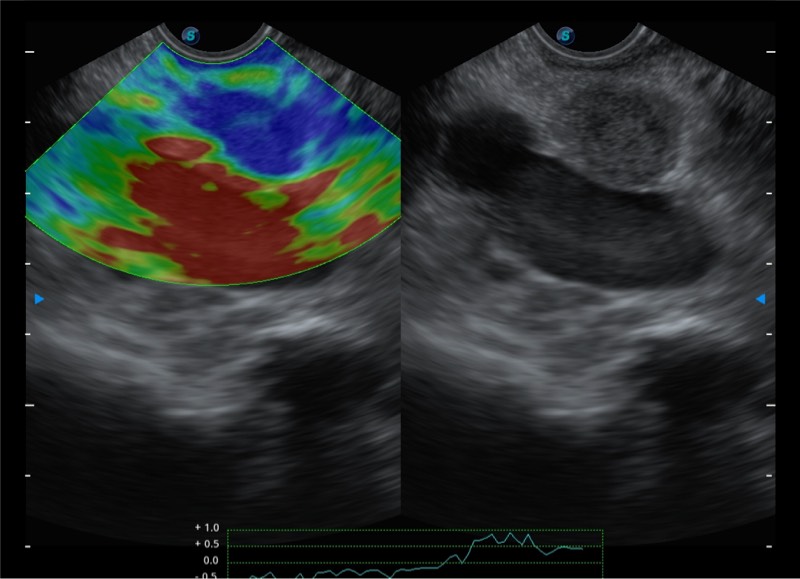

基于二十年的超声技术积累,球速体育入口提供了最新一代的独立超声主机,在提供高质量图像的同时满足多学科使用。具备常见多普勒技术并提供弹性成像、声学造影等高端影像技术。新一代传感器具有更强的抗干扰能力并减少图像伪影。